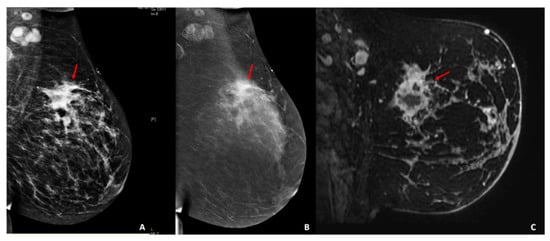

Radiomics for Tumor Characterization in Breast Cancer Patients: A Feasibility Study Comparing Contrast-Enhanced Mammography and Magnetic Resonance Imaging

Marino, M.A.; Leithner, D.; Sung, J.; Avendano, D.; Morris, E.A.; Pinker, K.; Jochelson, M.S. Radiomics for Tumor Characterization in Breast Cancer Patients: A Feasibility Study Comparing Contrast-Enhanced Mammography and Magnetic Resonance Imaging. Diagnostics 2020, 10, 492. https://doi.org/10.3390/diagnostics10070492